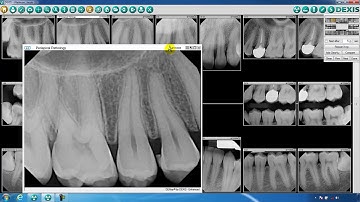

Launching DEXIS IS ScanFlow from DEXIS Imaging Suite Demo